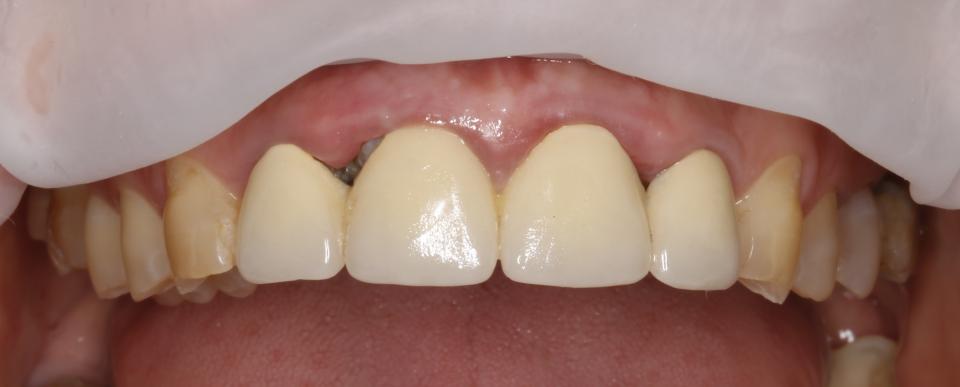

paraschyk1 Опубліковано: 6 червня 2018 Автор Опубліковано: 6 червня 2018 Вот фото зубов где коронки были сделаны пять лет назад с прайсом вдвое дороже чем у меня сейчас. Зубы после такого- трупы.А все от ненадлежащего качества работы и пох.зма в отношении в людям.

paraschyk1 Опубліковано: 6 червня 2018 Автор Опубліковано: 6 червня 2018 Вот фото где также коронки простояли четыре года и пац только выплатил кредит по ним,а спустя два мес. пришлось все убрать и переделывать,ессно за новые тугрики.